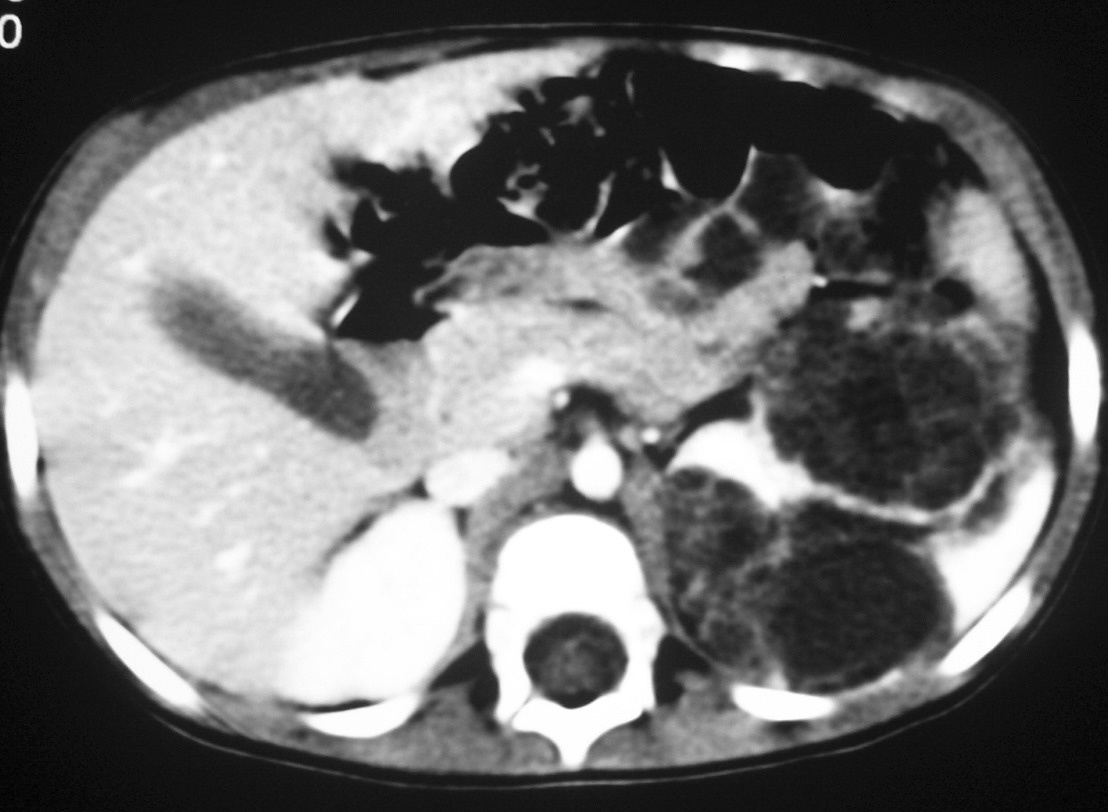

Los pacientes con diagnóstico histológico de tumor quístico multilocular (n = 7) tenían entre 5 meses y 12 años, siendo 4 de ellos varones y 3 mujeres. La clínica inicial fue la de masa abdominal palpable en 5, hematuria en uno y dolor abdominal en el paciente mayor. Se identificaron masas renales bien definidas que presentaban un aspecto quístico, con múltiples loculaciones separadas por septos que mostraban discreto realce (figs. 3 y 4). En un paciente se encontraron focos de blastema en las paredes de los septos en el estudio histológico.

Fig. 3. Tumor quístico multilocular. (A) Ecografía abdominal. Corte renal longitudinal. Masa renal heterogénea con predominio de áreas anecoicas. (B) Tomografía computarizada abdominal con contraste intravenoso. Corte sobre polo superior renal izquierdo. Masa de aspecto multiquístico que presenta zonas de parénquima renal sano entre las formaciones quísticas.

Los estudios radiológicos muestran una masa de gran tamaño, encapsulada, con múltiples quistes no comunicantes, que pueden herniarse hacia la pelvis y el uréter y cuyos septos presentan un realce irregular bajo o moderado4,8,9.